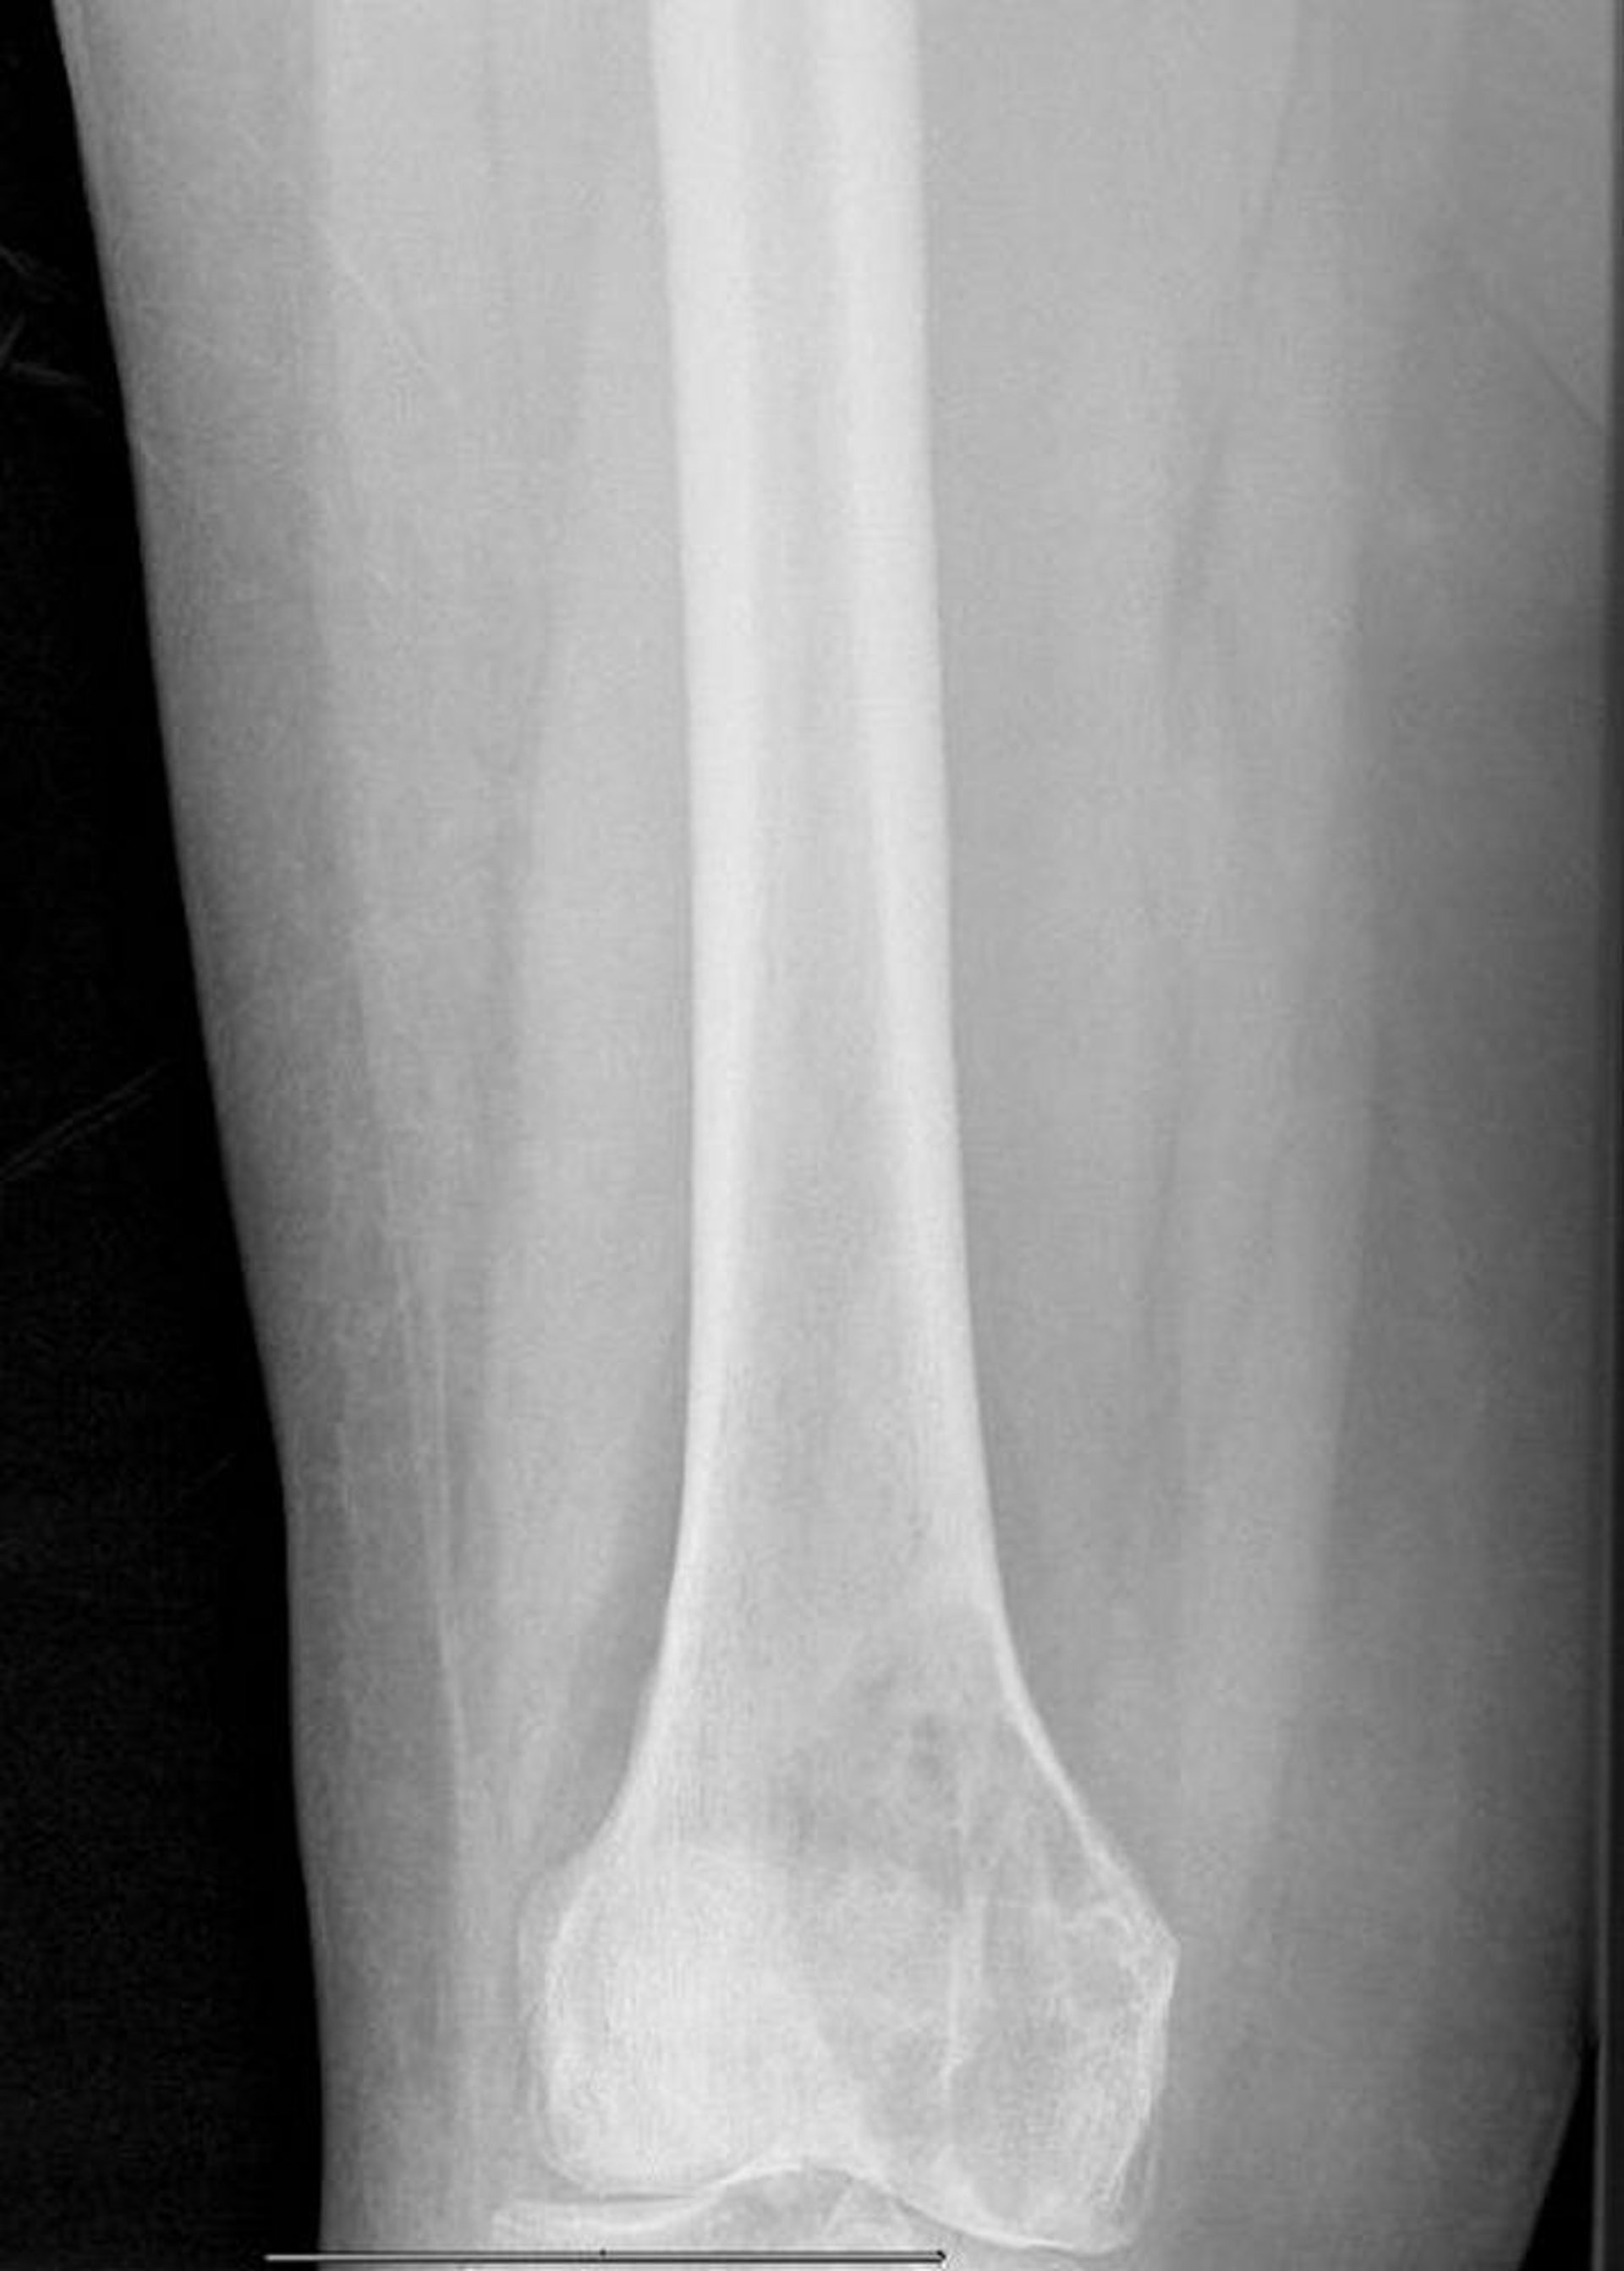

Metastasi litiche nel femore distale

Questa radiografia mostra un'ampia lesione litica metastatica del condilo mediale femorale con frattura patologica imminente.